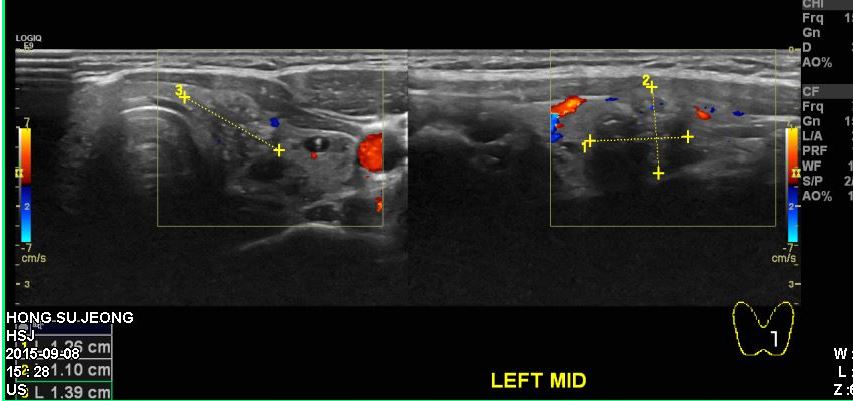

건강검진상 결절발견되어 내원하신 20대 여자분으로 본원에서 세포검사하신후,

왼쪽갑상선 유두암 진단되셨습니다.